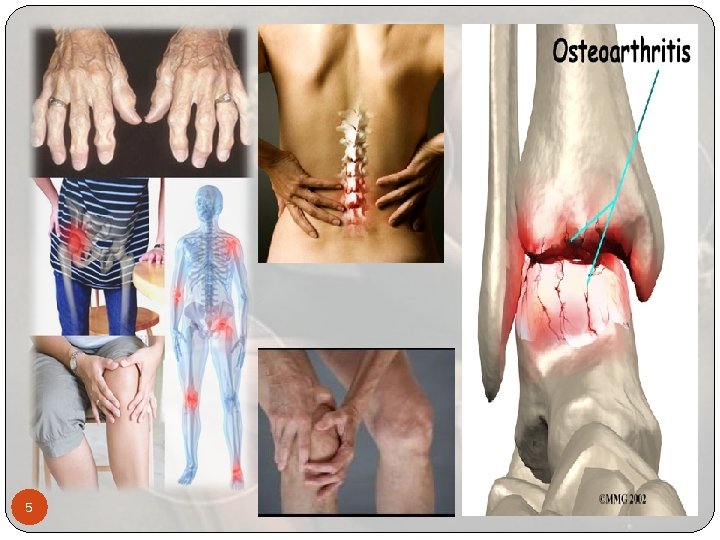

Osteoartritis: OA Enfermedad de las articulaciones o coyunturas Nombre alterno Trastorno degenerativo de las articulaciones o artrosis Afectando el cartilago y movimiento físico temporal o permanente Desgaste, fricción, espuelones (osteofitos) Causa dolor, hinchazon y perdida de los movimientos normales Manos, Rodillas, Caderas y Columna La osteoartritis es el tipo más común de artritis Solo afecta las articulaciones, no otros organos como la artritis reumatoide (R. A) que es el segundo más comun. Población: Edad avanzada, ciertos trabajadores, algunos deportes 3

Osteoartritis: OA La OA afecta a casi 27 millones de personas en Estados Unidos. Los síntomas de la OA típicamente inician a partir de los 40 años y avanzan lentamente Después de la edad de 50 años, las mujeres presentan más frecuencia de OA que los varones El costo promedio directo de la OA es aproximadamente $2 600 al año por persona con OA. 4

Signos y Síntomas El dolor y la rigidez en las articulaciones es el síntoma más comun El dolor con frecuencia es peor después del ejercicio y cuando usted pone peso o ejerce presión sobre la articulación. Usted puede notar un sonido de fricción, chirriante o crujiente al mover la articulación. La frase "rigidez matutina" se refiere al dolor y la rigidez que usted puede sentir apenas despierta por la mañana. La rigidez por lo regular dura 30 minutos o menos y mejora por la actividad leve que "calienta" la articulación 10

Signos y Síntomas Durante el día, el dolor puede empeorar cuando usted está activo Cuando está descansando, al rato, el dolor puede estar presente e incluso puede despertarlo por la noche. Algunas personas podrían no tener síntomas, aunque las radiografías muestren los cambios de la osteoartritis. 11